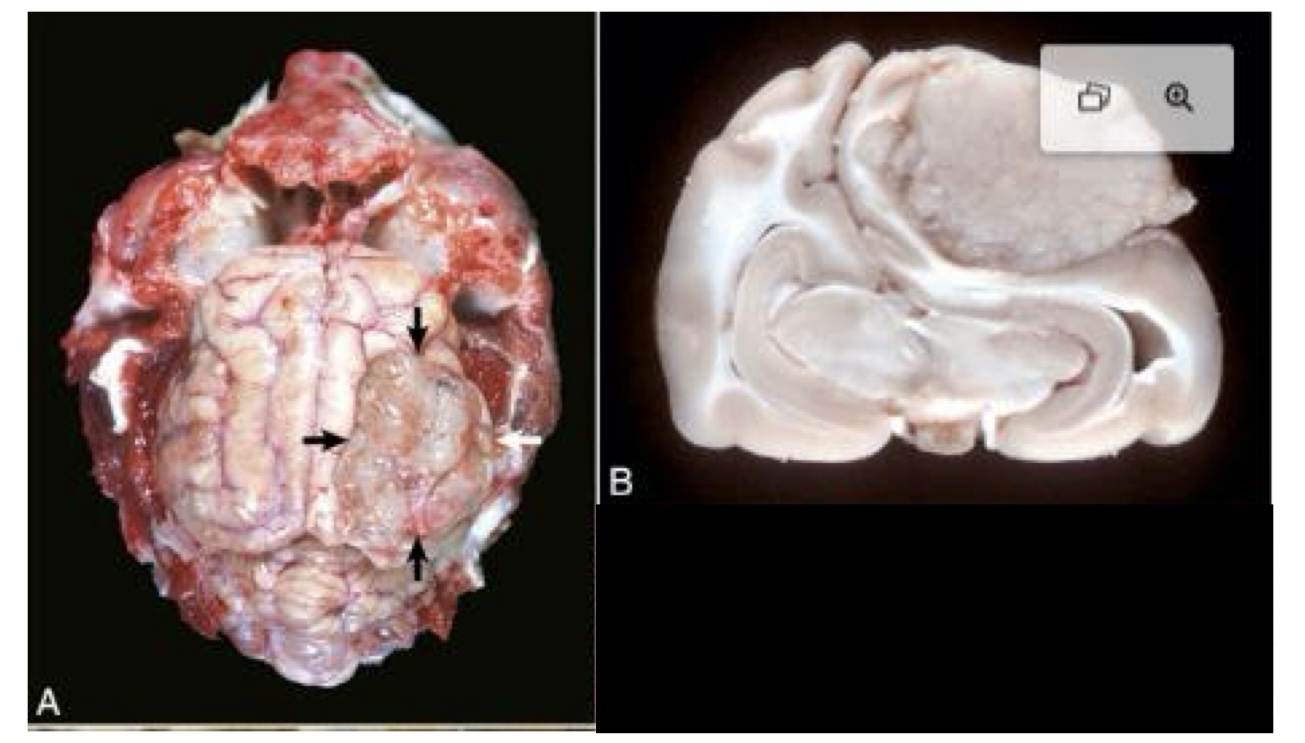

what is this?

metastatic hemangiosarcoma → prominent hematogenous metastases, which appear as black nodules of various sizes distributed throughout the brain

in an unfixed specimen, what color would the nodules of metastatic hemangiosarcoma be?

red to dark red